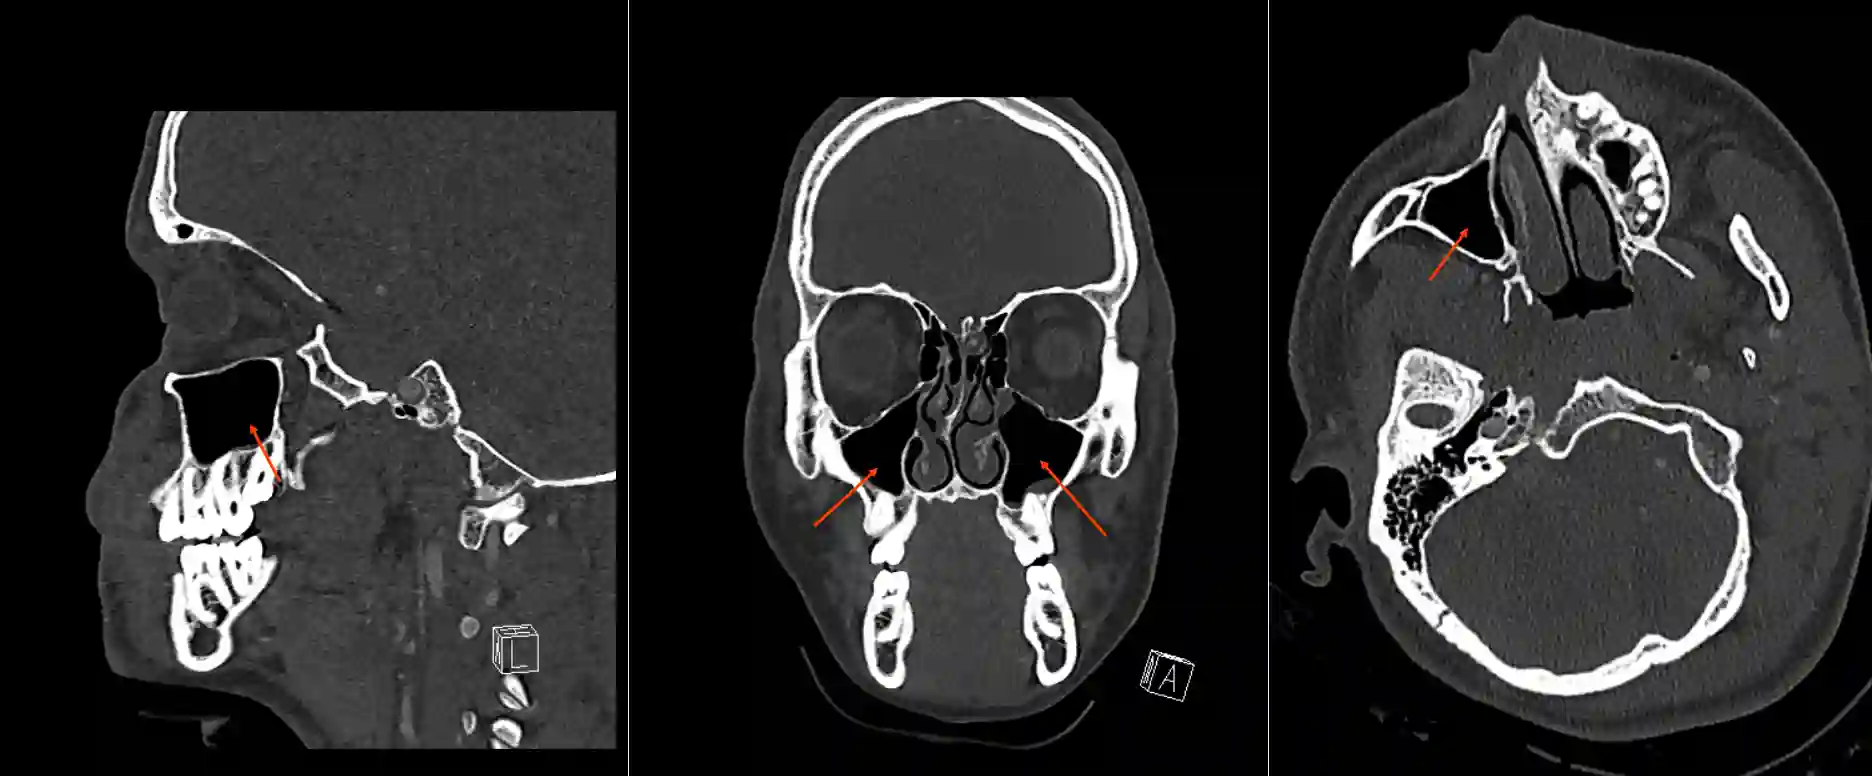

Sinus maxillaris im CT

Darstellung des Sinus maxillaris in drei verschiedenen Ebenen im CT Knochenfenster.